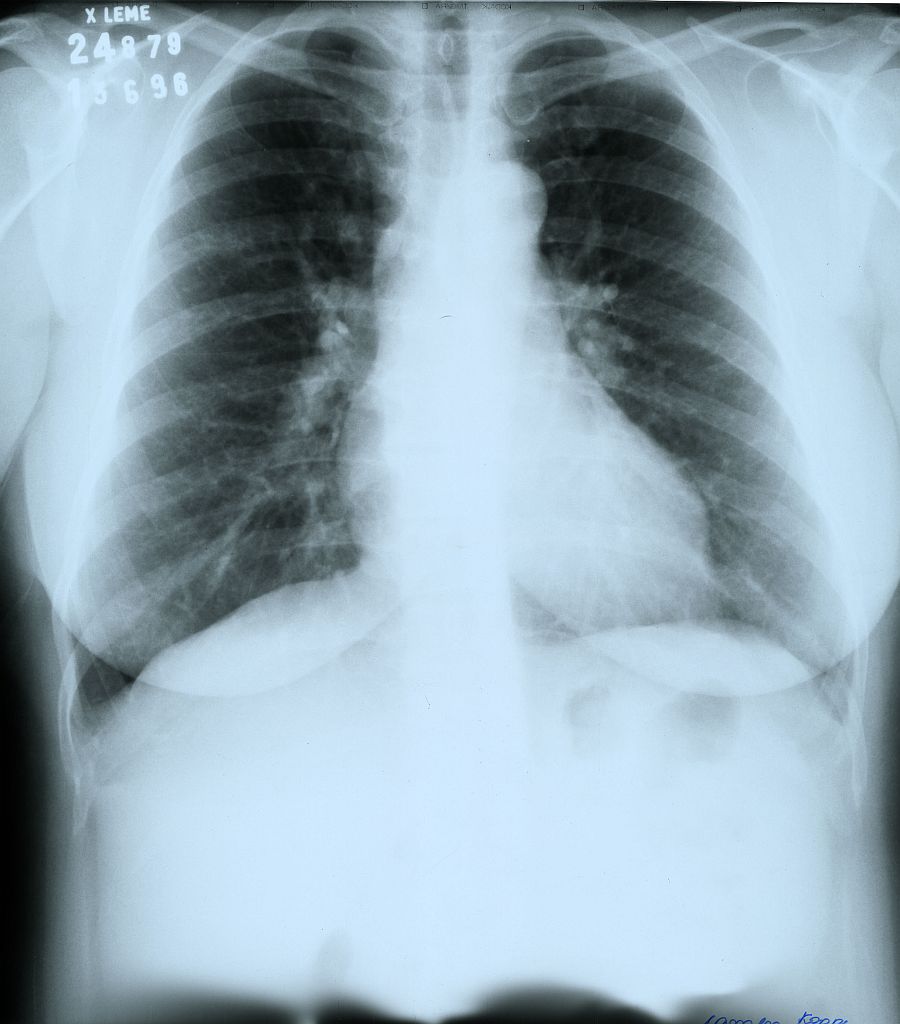

"O bacilo da tuberculose costuma se instalar na região superior dos pulmões, onde há mais oxigênio. Nesses locais, a bactéria forma uma cavidade e se multiplica em três áreas distintas: dentro e em volta da cavidade, e no interior dos macrófagos, células de defesa produzidas pelo organismo, que não conseguem matar os bacilos", explica o médico.